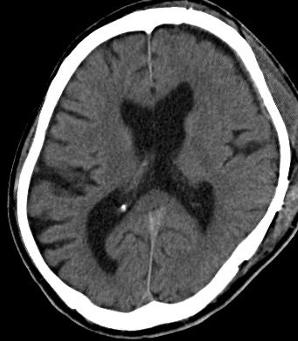

治る認知症があるのをご存知ですか?

はっきりとした原因がないのに歩きにくくなったり、認知症、尿失禁の症状が出た場合、「特発性正常圧水頭症」という病気の可能性があります。このような症状は、パーキンソン病や脳卒中、あるいはアルツハイマー型認知症などでもみられますが、数%の割合で、「特発性正常圧水頭症」という病気が含まれていることがあります。この病気は適切な診断ができれば、髄液シャント術という手術で症状の改善が得られます。また、当科の特色として、頭に傷をつけなくてもよい腰椎―腹腔シャント術(LPシャント)も積極的に行なっております。

(正常圧水頭症患者MR冠状断)

腰椎―腹腔シャント術後